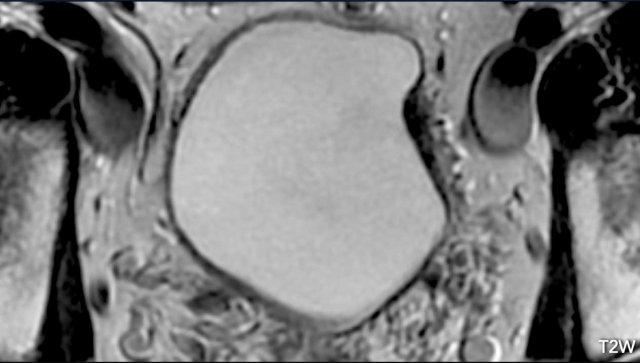

Hình ảnh

Có một khối u nhú lớn ở thành bàng quang bên trái xâm lấn vào đường giảm tín hiệu của cơ thành bàng quang.

Đây là trường hợp khó đánh giá vì có vẻ như có xâm lấn mỡ.

Tuy nhiên, hình ảnh T2W thường đánh giá quá mức xâm lấn mỡ do hiệu ứng thể tích từng phần.

Bước tiếp theo là đánh giá các hình ảnh DCE và khuếch tán để phân biệt giữa VI-RADS 4 và 5.